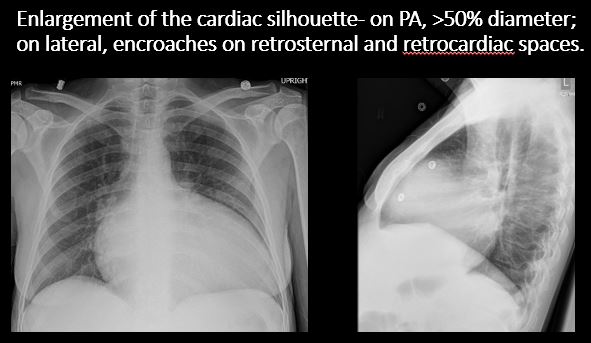

There is enlargement of the cardiac silhouette. |

No | NA |

There is an abnormality in the retrosternal, retrotracheal, or retrocardiac space on the lateral view. |